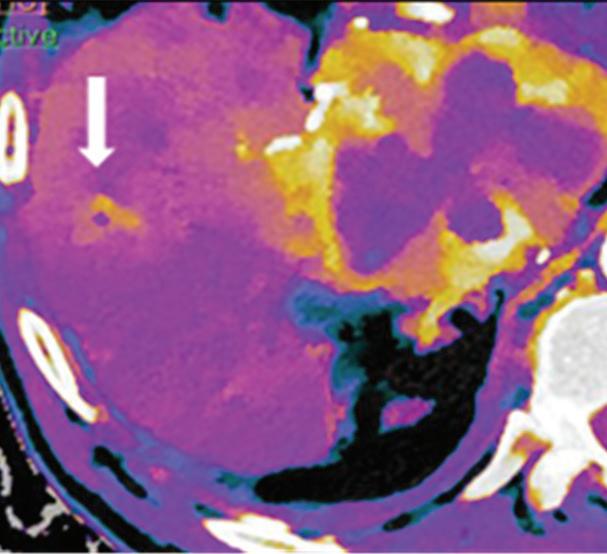

Renal and adrenal gland tumors. Contrast-enhanced-DECT images are particularly useful for the characterization of incidental renal or supra-renal lesions and for their follow-up, without the need of conventional unenhanced acquisition, translating into achieving a 30% mean dose savings for triphasic and up to 50% for biphasic renal protocols in daily clinical practice.17 It is also very useful in depicting hypervascular renal cell carcinoma metastasis in the liver or other sites, such as in the peritoneum and bowel wall (Figures 2 and 3).

Z effective

Spectral CT is able to generate Z effective images that show the mean atomic number of the material present in a voxel (Z effective values) and can be displayed as color coded overlay maps. Z effective images may be helpful to enhance the visual differences between different tissue types.46 Furthermore, due to the high atomic number of iodine compared to other tissues present in the human body, the Z effective images can highlight enhancing structures (Figures 2, 3, 4, and 5) and could be used for quantitative analysis to differentiate benign from malignant tumors or lymph nodes.16,45,47

Effectiveness of spectral CT imaging for detection of hypervascular liver metastases. A small hypervascular metastasis (arrow) from renal cell carcinoma. (a) Axial contrast-enhanced conventional CT image obtained in the arterial phase, corresponding (b) monoenergetic 50 keV, and (c) Z effective image.

Effectiveness of spectral CT imaging for detection of a peritoneal implant from a renal cell carcinoma invading the bowel wall (arrow). (a) Coronal contrast-enhanced conventional CT image obtained in the arterial phase, corresponding (b) Z effective, (c) monoenergetic 50 keV, and (d) iodine-density image.